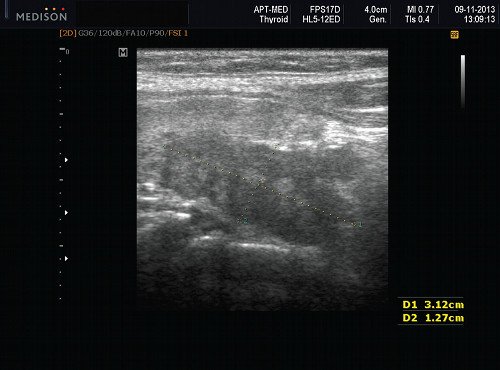

Диагностика рака щитовидной железы: как ультразвук помогает в раннем выявлении Рак щитовидной железы — это одна из наиболее часто встречающихся онкологических